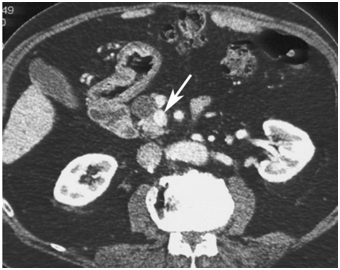

CT scan has many advantages since it can be easily performed, is non-invasive and the images are easily interpretable for the surgeon. Insulinoma typically appear as well-defined, rounded, homogeneously masses of the pancreas. Because the majority of insulinoma are usually smaller than 2cm, dynamic CT scan should be performed; the sensitivity of the dynamic CT scan in the detection of insulinoma ranges from 30% to 66%. Dual-phase contrast spiral CT scan is more sensitive than other noninvasive imaging studies. In a group of seven patients with tumors that were biochemically proven but not previously located by ultrasonography, CT scan, or magnetic resonance imaging, six of seven tumors ranging from 6 to 18 mm were detected by dual-phase spiral CT scan. Atypical CT scan imaging of insulinoma includes hypoattenuating masses on enhanced CT or intra-arterial dynamic CT, cystic masses, and calcified masses (Figure 1–3).26–30

Figure 2 Pancreatic insulinoma. Axial contrast-enhanced CT scan obtained during the arterial phase shows a homogeneous enhancing lesion (black arrow) in the uncinate process of the pancreas, just posterior to the superior mesenteric vein (white arrow). 24